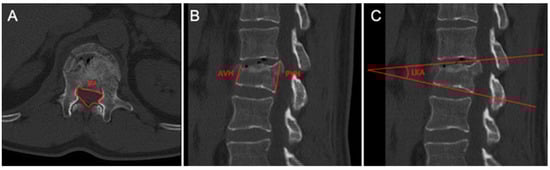

- Spinal canal area (SCA): the area of the spinal canal at the level of maximum bone fragment retropulsion.

- Anterior vertebral height (AVH) (mm): the distance between the antero-superior and antero-inferior edge of the fractured vertebra, measured at the level of the anterior vertebral body wall.

- Posterior vertebral height (PVH) (mm): the distance between the postero-superior and postero-inferior edge of the fractured vertebra, measured at the level of the posterior vertebral body wall.

- Local kyphotic angle (LKA): the angle formed by a line drawn along the superior end plate, considering the apex of the protruded fragment, and the inferior end plate of the fractured vertebra.

- Position of the fragment block: evaluated on the axial plane at CT scan; the posterior wall of the fractured vertebra at the level of the spinal canal was divided into three equal sectors, defining the fragment as lateral (left or right), paramedian (middle-left/-right), or median.